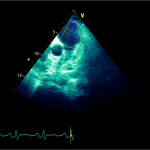

Ecocardiografia transtoracică

- Formaţiune hiperecogenă cu suprafaţa neregulată, care tapetează peretele liber al VD, grosime de 12 mm

- Dispusă de sub planul valvei tricuspide până in apropierea conului de ejecţie al valvei pulmonare

- SIV aplatizat

Ecografia transesofagiană:

Confirmă datele de la ecografia transtoracică